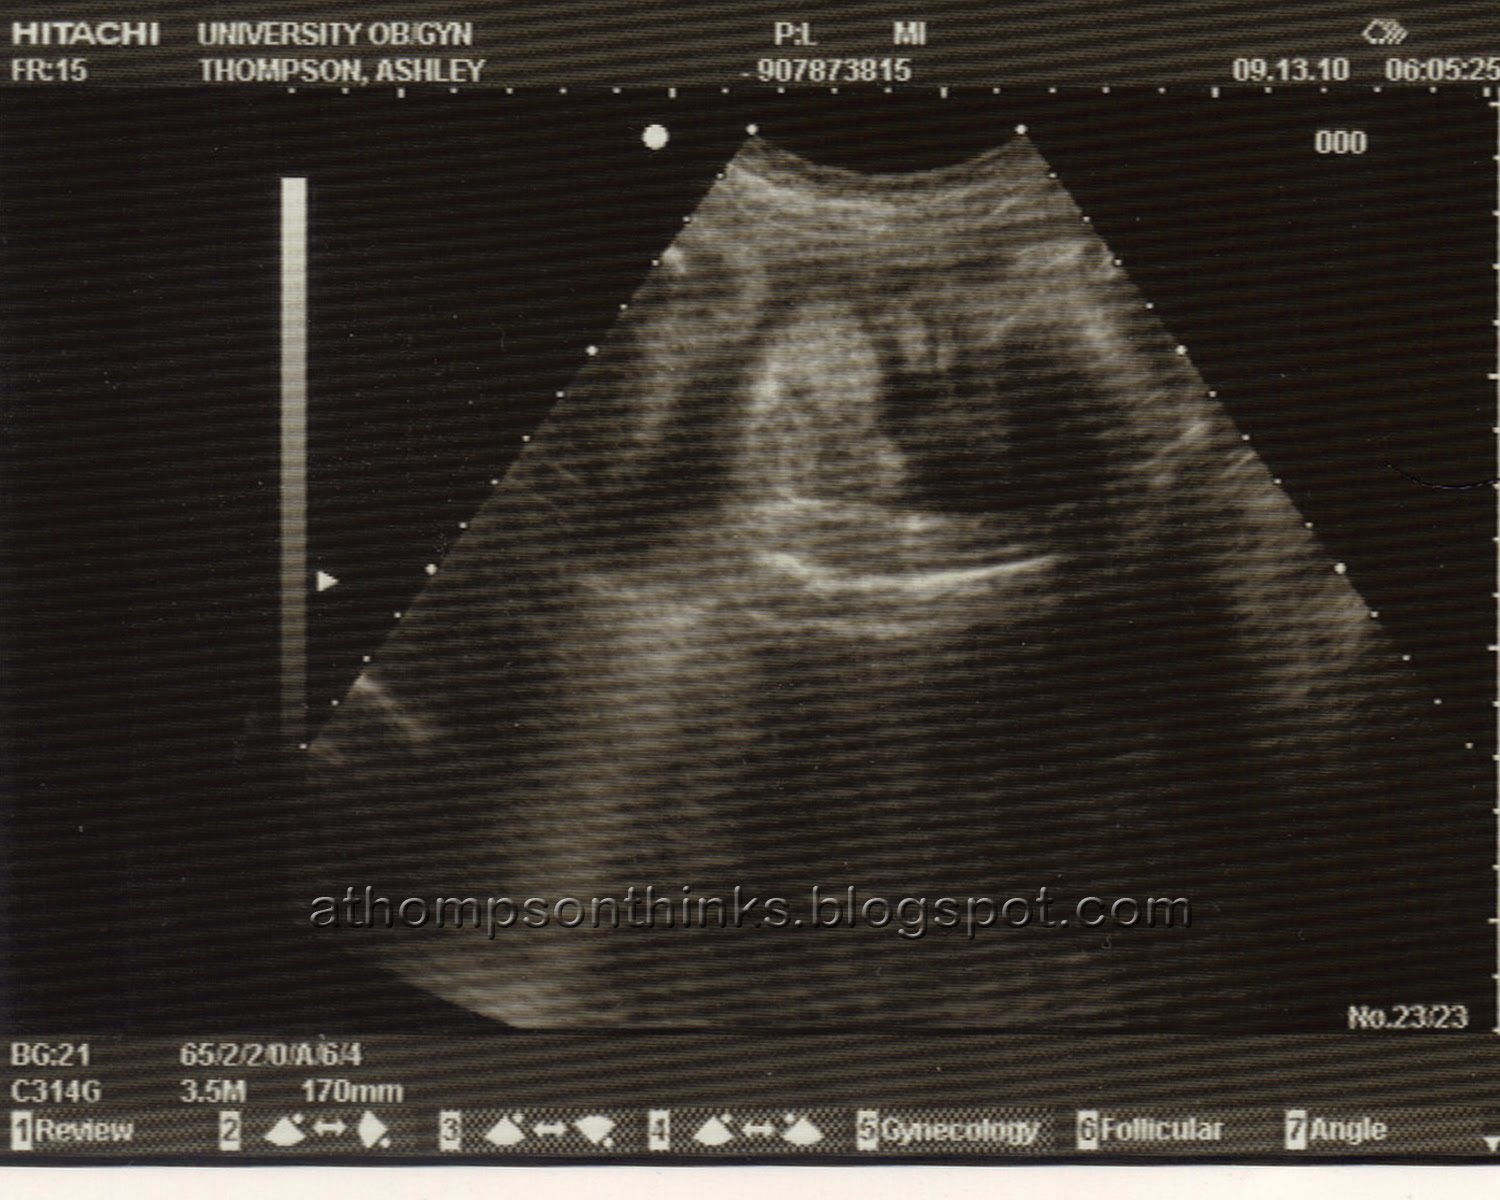

Here is my ity bity! You can see one of his eyes and his lips… one of his arms is over his face covering it. I can’t wait to hold my little boy!